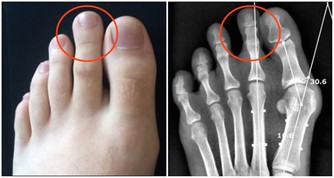

這種吃法曾被腎內科醫生稱為“最傷腎的吃法”。大量吃海鮮會產生過多的尿酸和尿素氮等代謝廢物,加重腎臟排泄負擔。而大量喝啤酒的話,腎臟發生疾病的機率會增高,也會讓尿酸堆積在腎小管裡面而出現堵塞情況,情況嚴重的人還容易造成腎臟衰竭。